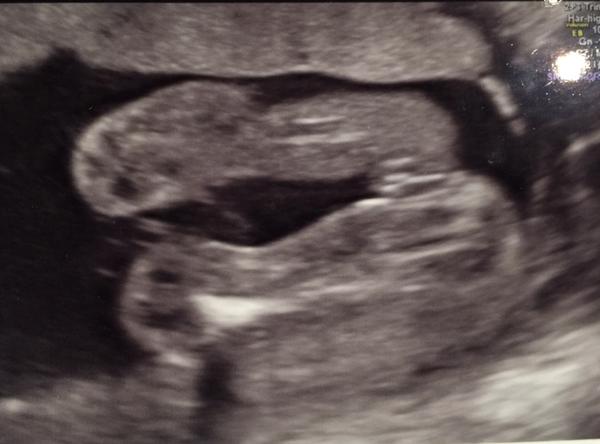

Je to holčička nebo chlapeček? Foto ultrazvuku

@relax84 podle mě je to holčička ;) mně ji potvrdili teda až ve 20tt, protože měla pořád nožky křížem, ale vypadá to takto

No já vidím opravdu jasnou holčičku 🙂 tady snad nekdo o zom pochybuje,mam 3syny a obrázky jsem měla jiné relax85,nvo jineho by bylo kdyby nebyly nozicky takhle od sebe,kdyby to byl klučík,tak by výrazně čouhalo něco dopředu , ;) 🙂